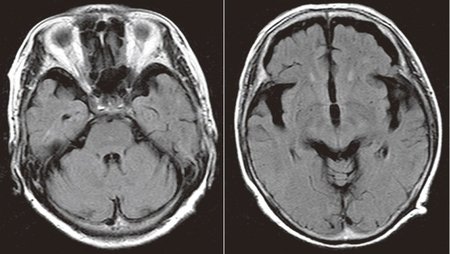

60代後半女性。2年前から記憶があいまいに。家事に無関心・無気力、肉じゃがを作れない。日にちが分からない。めまいがする。朝から起きていられない、ふらふらする。本やテレビを見ていると気分が悪くなってくる。HDS-R13点、MMSE13点。両側前頭葉および両側側頭葉の萎縮が目立つ。海馬の萎縮は認めない

[図表1]前頭側頭型認知症のMRI像 60代後半女性。2年前から記憶があいまいに。家事に無関心・無気力、肉じゃがを作れない。日にちが分からない。めまいがする。朝から起きていられない、ふらふらする。本やテレビを見ていると気分が悪くなってくる。HDS-R13点、MMSE13点。両側前頭葉および両側側頭葉の萎縮が目立つ。海馬の萎縮は認めない